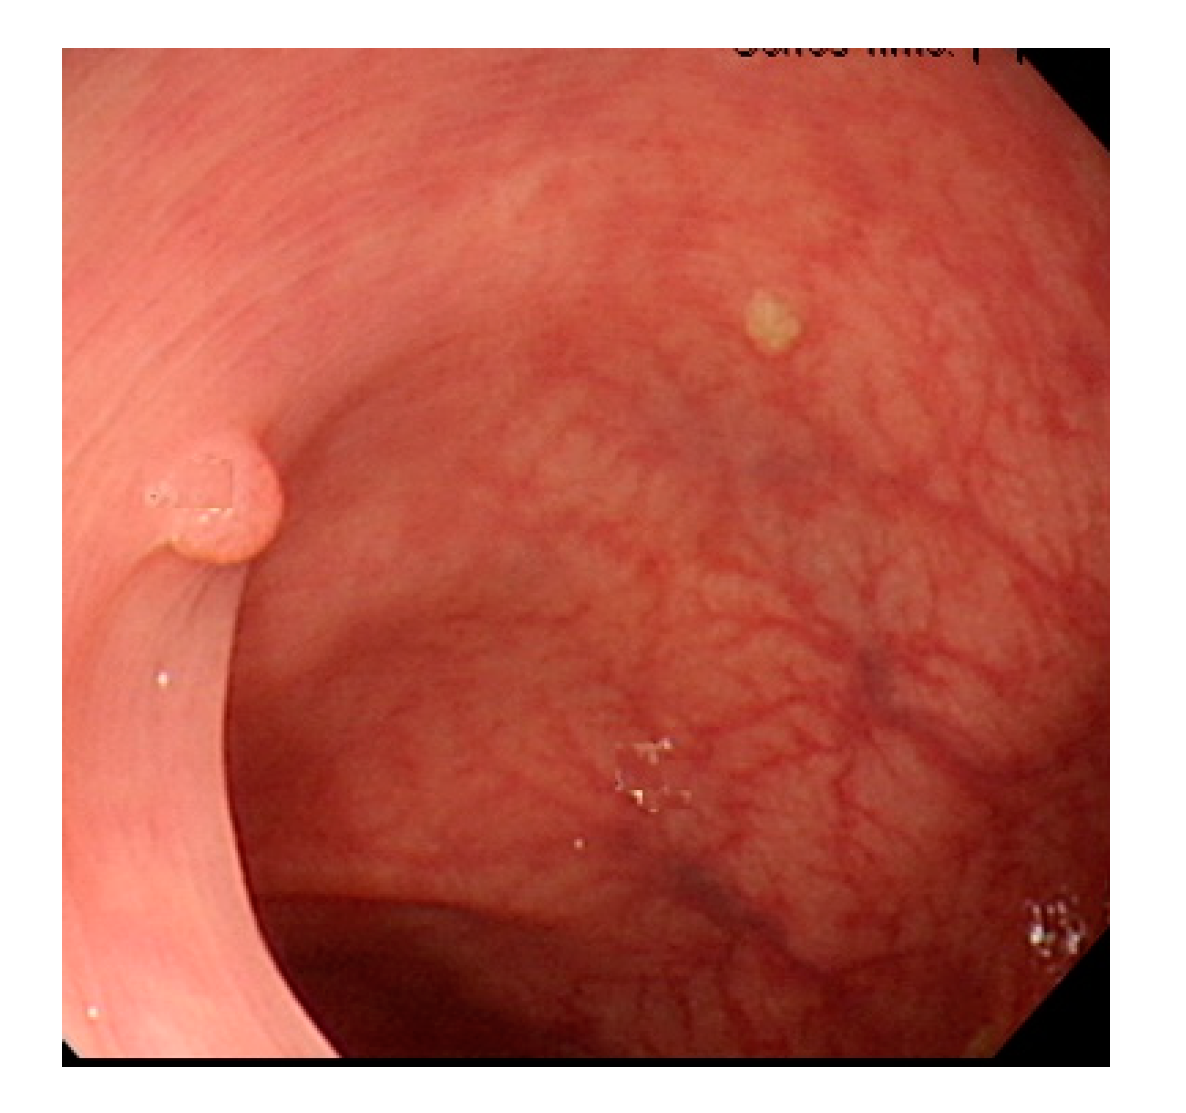

Currently, many medical images are processed into grayscale images, such as ultrasound, computed tomography (CT), and magnetic resonance (MR) images. Tan et al. [44] applied a gray-level cooccurrence matrix and CNN to CT images for polyp diagnosis. Zhang et al. [45] compress the three-channel color images of chest CT to grayscale images. A five-layer deep CNN with stochastic pooling is used to diagnose chest-based COVID-19. Xie et al. [46] mentioned that in deep learning, colors are not the key features influencing accurate image classification. They also discovered that in X-ray image classification, the speed and accuracy of processing grayscale images were considerably higher than those of processing RGB images. The grayscale method used was ITU-R Recommendation BT.601 [47]. Moreover, misjudgments were easily made in the presence of excessive intestinal wall textures, when polyps were too small (Figure 2), and when polyp textures were similar (Figure 3) to intestinal wall textures.

Figure 2. Excessive intestinal wall textures with small polyps.